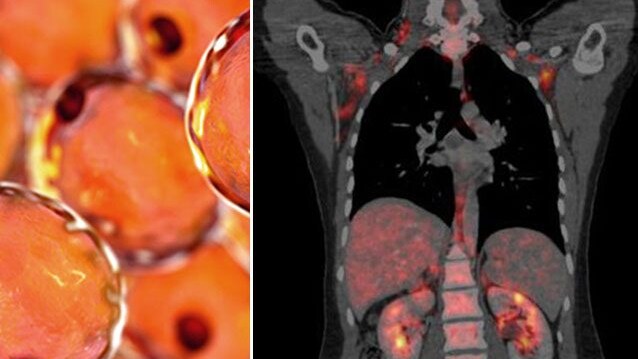

La virologa Halassy cura il suo tumore al seno iniettandosi due virus: i risultati dell’auto-sperimentazione

Più casi e più morti di cancro entro il 2050, cosa dice lo studio che prevede quasi il doppio dei decessi